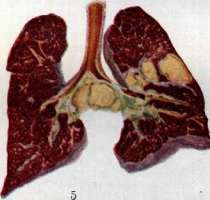

гематогенной генерализацией в результате проникания туб. бацил в ток крови непосредственно или через посредство лимфы (см. Туберкулез). В легких гематогенное поражение проявляется разно. При обшем милиарном Т. в обоих легких наблюдается высыпь массы милиарных туберкулов [см. отд. табл. (ст. 119—120), рис. 3]; в этих случаях ткань легких представляется полнокровной и на таком фоне видны бугорки в зависимости от возраста и типа их или мелкие, серые, полупрозрачные или желтые, с неровными контурами, часто более крупные. Нередко можно, согласно указанию Рибберта (1902), заметить, что у взрослых в верхних районах легких бугорки несколько более крупны, чем в нижних, что объясняют более энергичным ростом туберкулов именно в верхних отделах легких. Если проникание туб. бацил произошло в ветвь легочной артерии, то мидиариза-ция захватывает лишь соответствующую часть легочной территории. Микроскоп, исследование при милиаризации в легких может открыть разный тип бугорков: иногда это типичные продуктивные эпителиоидные бугорки, имеющие своим источником развития альвеолярные перегородки; бугорки растут, сдавливая и уничтожая альвеолы и оставаясь долго продуктивными бугорками; в других случаях к бугорку, начавшему развиваться в альвеолярной перегородке, быстро присоединяется эксудация в альвеолы; наконец бывает так, что бугорок как бы сразу возникает в виде милиарной пневмонии, захватывающей 2—4 соседних альвеолы (милиарный альвеолит), и таким образом обнаруживает экеудативный характер. Гюбшман и Шлейсинг выдвигают ту точку зрения, что всякий бугорок в легких начинается в виде милиарной пневмонии и уже потом окружается продуктивной зоной. Эта точка зрения вызвала категорические возражения крупнейших патологов (Герксгеймер, Ашоф, Штернберг и др.); кроме того Гретман (Grethmann, 1928) установил, что гематогенные милиарные бугорки в легких как правило развиваются в виде продуктивных бугорков из стенок мелких сосудов; эксудация в альвеолы есть явление последовательное, частое, но не обязательное. Гематогенное метастазирование в легкие может еще происходить в виде появления в легких одного или нескольких туб. очагов; по своему существу такая форма есть частное проявление органного T.j возникающего в порядке поздней генерализации первичного Т. (см. Туберкулез). Судьба и выражение таких отдельных гематогенных фокусов в легких бывает разной (см. ниже). Попытка Симона (Simon) объяснить все верхушечные рубцы, встречаемые в легких взрослых, гематогенным метастазированием, происходящим в детстве, у патологов не имела успеха; такое гематогенное метастазирование в верхушку легкого в детском возрасте встречается редко и на детских трупах мы не встречаем ничего похожего на начало образования этих очагов; верхушечные рубцы легких наблюдаются почти только у взрослых, и частота их возрастает с возрастом. Первичный Т. приводит к смерти детей или в связи с значительным распространением туб. процесса в легких или в связи с генерализацией, особенно в виде общего милиарного Т. и туб. менингита, У взрослых первичный Т. легких бывает очень редко; чаще всего это касается тех народностей, к-рые в детском возрасте не соприкасаются с туб. вирусом (см. Туберкулез).—В торичный Т. легких представляет собой то, что принято выделять в качестве легочной чахотки взрослых; по существу это—вспышка туб. процесса, или реинфект в легком у индивидуума, к-рый уже перенес первичную инфекцию и является относительно иммунным к туб. вирусу. Главной особенностью вторичного Т., или реинфекта является то, что процесс протекает б. или м. изолированно в легком, не обнаруживая склонности к лимфогенным и гематогенным метастазам. Если пат. анатомия легочной чахотки взрослых уже давно разработана достаточно хорошо и представляется б. или м. ясной, то этого нельзя сказать относительно патогенеза начальных изменений. В прежнее время, когда еще не делалось различий между Т. детского возраста и Т. взрослых, когда еще не было ничего известно по поводу первичного и вторичного Т., аллергии и пр., казались совершенно очевидными два обстоятельства: 1) легочная чахотка взрослых есть следствие аэрогенной инфекции легкого туб. палочкой; 2) легочная чахотка взрослых всегда начинается в области верхушки легкого. Изучение строения начальных фокусов Т., обнаруживаемых в верхушках, показало (Birch-Hirschfeld,1899; Schmorl,1901), что в них дело идет о туб. поражении стенки апикального бронха и развитии в таком месте бронхита с перибронхитом. Абрикосов (1904) при своих исследованиях начальных туб. очагов верхушек пришел к несколько иному заключению; он нашел, что поражение обычно начинается ниже, именно в районе 2-го дорсального субапикального бронха верхней доли и что фокус имеет бронхопневмонический характер. Абрикосов высказался за то, что процесс начинается со стенки внутридольковой бронхиолы и быстро принимает бронхопневмонический характер. Эти исследования подвели как бы фактический фундамент под теорию аэрогенного происхождения легочной чахотки; отчасти в связи с этим взгляды Ауфрехта (Aufrecht, 1900) и Рибберта (1901) о гематогенном происхождении легочного Т. взрослых не имели никакого успеха. После того как выдвинулось положение о патогенетическом отличии Т. детского возраста и Т. взрослых и сущность этого отличия была разъяснена в учении Ранке (см. Туберкулез), стало очевидным, что так просто смотреть на генез легочной чахотки взрослых, как это делалось раньше, нельзя. Раз оказалось, что легочная чахотка взрослых есть Т. организма, уже перенесшего туб. инфекцию, то естественно стали говорить, что в основе Т. взрослых лежит вторая инфекция, или реинфекция туб. вирусом. Механизм этой реинфекции понимался различно. По учению Ранке, реинфекция представляет собой не что иное, как обострение-изменений, относящихся к первичному Т. детского возраста (эндогенная реинфекция); т. о. Т. взрослых есть продолжение Т., идущего с детского возраста, но обостряющегося у взрослого, находящегося в состоянии относительного иммунитета к туб. вирусу. В противоположность этому Ашоф и др. стали настаивать на том, что легочная чахотка взрослых в громадном большинстве случаев есть следствие новой аэрогенной инфекции легкого, т. е.— экзогенная реинфекция или суперинфекция организма, уже перенесшего первичную.инфекцию. В последние годы очень многие фтизиатры склонились к мнению, что легочная ча- хотка взрослых есть следствие эндогенной реин-фекции по гематогенному пути. Источником такого гематогенного метастазирования в легкое являются или очаги первичного комплекса в легком и в лимф, железе средостения или туб. фокус в каком-нибудь органе, развившийся в порядке органного туберкулеза. Другой спорный пункт, выявившийся в последние годы, касается места начала легочной чахотки взрослых. До 1925 г. учение о том, что легочная чахотка начинается с самой верхушки легкого к что встречающиеся в верхушках рубцы с петрификатами и без них являются как раз выражением такого начала, не получившего в дальнейшем развития (зажившие очаги реинфекта), казалось совершенно незыблемым. В 1925 г. Асман (Assmann), в 1926 г. Редекер (Redeker), а в ближайшее время Ульрици, Ромберг, Лидтин (Romberg, Lydtin) и мн. др. на основании клинических и рентгенологических данных стали настаивать на том, что вышеуказанные верхушечные очаги никакого отношения к началу легочной чахотки не имеют, что легочная чахотка начинается не в верхушке, а в той области верхней доли, к-рая проецируется непосредственно ниже ключицы; как раз здесь начинается процесс в виде очага пневмонии, что и было обозначено как и н -ф р а к л а в и к у л я р н ы й (подключичный) инфил ьтрат или ранний ту б. инфильтрат (нем. Fruhinfiltrat). С такой точкой зрения не могли согласиться патологоанатомы (Ашоф, Graff, Гюбшман, Loeschke и др.), которые утверждали, что инфракдавикудярный инфильтрат не есть анат. начало легочной чахотки, а лишь клинико-рентгенологическое выявление процесса, начавшегося в верхушке и протекавшего до того без ясных клин, симптомов. На специальном туб. конгрессе в Вильд-баде (1928) и на съезде патологов в Вене (1929) это противоречие еще не было устранено. Однако в самое последнее время мы видим значительное смягчение указанного спора, связанное с тем обстоятельством, что, с одной стороны, патологоанатомы (Ашоф, Штернберг, Pa-gel, Schtirmann и др.) склонились к допущению возможности начала туб. процесса у взрослых с подключичной области, а с другой стороны, и клиницисты (Лидтин, Асман, Star linger, Рубинштейн и др.) согласились с тем, что инфракдавикулярный инфильтрат вовсе не обязательно является самостоятельным начальным фокусом Т., он может развиваться и последовательно из предсуществовавшего лятентного очага. Одновременно стали определенно говорить, что реинфект, являющийся началом легочной чахотки взрослых, может иметь как эндогенное, так и экзогенное происхождение. Т. о. в наст, время допускаются разные способы происхождения легочной чахотки взрослых и разные типы ее начала. Происхождение ее может быть в результате экзогенной (аэрогенной) и эндогенной реинфекции; эндогенная реинфекция развивается гематогенно или непосредственно из старого очага в легком (по соприкосновению иди бронхогенно). В смысле своего начала процесс может исходить из верхушечных очагов иди начаться в подключичной области. К этому надо еще прибавить возможность развития легочной чахотки взрослых из туб. лимф, желез ворот легкого. Последний способ образования реинфекта в легком является однако сравнительно редким; поэтому практическое значение имеют два спо- соба начала легочной чахотки: из верхушки легкого и из подключичной области его. С этим в наст, время согласно большинство патологов и клиницистов (Ашоф, Pagel, Schilrmann, Асман, Лидтин, Рубинштейн, Угрюмов, Штеф-ко и др.). Однако нет еще полного согласия в том, какой способ начала является более частым; у клиницистов имеется склонность считать инфраклавикулярное начало более обычным и указывать, что верхушечное начало наблюдается, лишь в 7—1Q% случаев Т. (Ромберг). С другой стороны, патологоанатомы на основании секционного материала устанавливают, что случаи с верхушечным началом относятся к случаям с подключичным началом, как 4 : 1 (Pagel, Угрюмов), т. е., что начало с верхушки легкого в 4 раза чаще, чем начало с инфракла-викулярной области. Совершенно открытым считается вопрос о том, насколько часто аэрогенное (экзогенное) и насколько часто гематогенное (а также другого типа эндогенаое) развитие реинфекта. Большинство указывает, что инфракдавикудярный очаг имеет гематогенное происхождение, тогда как верхушечные очаги могут иметь аэрогенное и гематогенное происхождение. В противоположность этому Нейман и Штарлингер (Neumann, Star linger) считают, что как раз ранний инфракдавикудярный инфильтрат есть результат аэрогенной (бронхогенной) суперинфекции, тогда как верхушечные очаги имеют гл. обр. гематогенное происхождение. Оставляя в стороне эти еще неясные и спорные пункты генеза легочной чахотки, коснемся пат. анатомии: 1) верхушечных очагов и 2) ин-фраклавикулярных инфильтратов. 1. Понятие «верхушка легкого» не у всех авторов одинаково; одни под «верхушкой» понимают лишь самый купол верхушки (нем. Кирре), другие—верхнюю треть верхней доли. Разное понимание является одной из причин несогласного толкования у авторов локализации верхушечных очагов. Надо заметить, что у взрослых предрасположенной к Т. является вся верхняя треть верхней доли легкого, в к-рой и встречаются верхушечные очаги реинфекта. Предрасположение этой верхней части легкого к Т. по современным воззрениям (Ors6s, Loeschke) связано с тем, что на ней наиболее сильно сказывается влияние тяги диафрагмы, создающей здесь малокровие и ателектатическое состояние легочной ткани вследствие сдавления сосудов и бронхов; это проявляется особенно сильно у лиц с астенической грудной клеткой. Относительно числа и локализации верхушечных реинфектов наиболее точные данные представляются Шюрма-ном: в 40,8% всех реинфектов обнаружен 1 очаг, в 26,4%—2—4 очага, в 23,2%—5—10 очагов, в 9,6%—более 10 очагов. Множественные реин-фекты могут иметь одинаковый возраст, что говорит за одновременное их образование, или же представляют разную степень развития, что свидетельствует о разном сроке их возникновения и м. б. зависимости друг от друга. В 37,4% реинфекты имелись только в правом легком, в 30,1% — только в левом, в 32,5%—в обоих легких. В 40% очаги лежали в самом куполе верхушки, в 60% пальца на два ниже купола (Абрикосов также находил, что начальные очаги обычно лежат не в самом куполе, а в районе субапикального бронха). По Стру-кову 00,4% очагов встречаются в правом легком, 23,2%—в левом, 16,4%—в обоих легких. Х17 Внешний вид верхушечных очагов может быть разным. Размеры их колеблются от 2 до 15 мм в диаметре. Иногда очаг представляет собой просто ограниченное утолщение плевры, на разрезе к-рого обнаруживается слой плотной хрящеподобной соединительной ткани без каких-либо творожистых гнезд и петрификатов, в других случаях это — антракотический очаг, тоже располагающийся плеврально, далее идут втянутые рубцы, связанные с плеврой и сопровождающиеся образованием синехий между париетальной и висцеральной плеврой; они могут быть без петрификатов или с ними; наконец часто встречаются казеозные и петри-фицированные очаги, расположенные в отдалении от поверхности и находящиеся в связи с плеврой или лежащие свободно в легочной ткани без связи с плеврой. Имеется склонность (Штефко) подразделять эти очаги на: 1) интра-пульмоналыгые и 2) плевропулъмональные (экстрапудьмональные, плевральные) с подразделением интрапульмональных очагов (Стру-ков) на: а) классические верхушечные реинфек-ты(аэрогенные) и б) очаги Пуля (гематогенные). Другие, выключая плевральные очаги как не-слецифические, рассматривают отдельно Симоновские и Пулевские очаги и т. д. Описания этих отдельных типов верхушечных очагов и их квалификация далеко не совпадают у разных авторов, что заставляет считать вышеуказанные классификации, точно так же как определение одних очагов как гематогенных, других—как аэрогенных, весьма субъективными и шаткими. Если плевральные утолщения и антракотические узелки без казеоза и петрификатов не считать относящимися к Т., то получается, что реинфекты встречаются в 50— 60% всех трупов взрослых; если же квалифицировать как tbc также и плевральные утолщения, рубчики, антракотические узелкрг (как это делают Ашоф, Focke, Anders и др.), то оказывается, что очаги реинфекта встречаются на трупах взрослых не реже, чем первичный аффект, т. е. в 95—98%. По современным воззрениям всякий реин-фект в самом начале его развития представляется в виде очага «раннего инфильтрата», т. е. пневмонического фокуса с весьма слабыми про-лиферативными явлениями; это конечно еще не исключает того, что и до вспышки пневмонического процесса в стенке бронхиолы имелся туб. очажок, к-рый и является началом всего процесса. Очаг пневмонии может подвергнуться обратному развитию, рассасыванию, чаще однако он претерпевает творожистое перерождение и инкапсуляцию. Инкапсулированные очаги реинфекта, Пулевские или Ашоф-Пулев-ские очаги, как их называют (в противоположность Гоновским очагам первичного аффекта), очень полиморфны по своему виду; они то круглы, то овальны, то состоят из группы отдельных узелков, нередко ориентированных по разветвлениям мелкого бронха; особенностью их является нерезко выраженная и сравнительно поздняя петрификация, отсутствие образования в капсуле костной ткани, толстая неспецифическая капсула с углем и с распространением соединительнотканного разрастания с лимфоидными скоплениями на соседнюю легочную ткань; нередко образование соединительнотканных тяжей, связывающих капсулу с плеврой, с сосудами и бронхами. Иногда вокруг очага легочная ткань па большом протяжении ателектатична, склерозирована, ан- тракотична, с бронхоэктазами. Как показывает бактериол. исследование инкапсулированных и петрифицированных очагов реинфекта, в них долго содержатся вирулентные туб. бацилы. Кроме того и микроскоп, исследование нередко вокруг таких казалось бы совершенно заживших очагов открывает свежие бугорки. Поражения регионарных лимф, желез при реинфек-тах не бывает; иногда в железах наблюдаются лишь отдельные бугорки. Как уже указано, в наст, время взгляд, что верхушечные реинфекты могут быть источником легочной чахотки, т. е. прогрессирующего Т., является общепринятым. Развитие туб. процесса из верхушечных очагов происходит 4 способами: 1) иногда образовавшийся реинфект непосредственно увеличивается и образует крупный пневмонический очаг (верхушечный инфильтрат), к-рый в дальнейшем прогрессирует; 2) в других случаях рядом с как бы зажившим реинфектом по соприкосновению появляются свежие бугорки и очаги пневмонического типа; 3) очаг реинфекта, расположенный у стенки бронха, дает прорыв в бронх и развитие бронхогенных метастазов как вблизи, так и в отдалении от очага; 4) из реинфекта процесс распространяется лим-фогенно по ходу бронха, давая туб. периброн-хит, а в дальнейшем и туб. бронхит с бронхо-гешгой диссеминацией. Лешке считает эти два последних пути самыми частыми типами начала легочной чахотки взрослых и даже инфракла-викулярный инфильтрат квалифицирует как бронхогенный метастаз из верхушечного реинфекта. 2. Инфраклавикулярный ранний инфильтрат с патологоанатомической стороны описан небольшим числом авторов (Асман, Zadek, Schurmann, Pagel, Штефко, Рубинштейн и Пожариский, Угрюмо в); зависит это от того, что в периоде раннего инфильтрата больные не умирают, вследствие чего ранний инфильтрат в большинстве случаев можно уловить на секционном столе лишь в качестве случайной находки у б-ных, умерших от других б-ней. Анатомически инфраклавикулярный инфильтрат представляет очаг острой се-розно-фибринозной пневмонии с колятераль-ным отеком; такой очаг может в дальнейшем рассосаться, оставив после себя лишь небольшой склероз легочной ткани, или же подвергается творожистому перерождению, представляя в этом случае однородное казеозное поле величиной в 2—3 см в диаметре; казеозный очаг может инкапсулироваться и петрифициро-ваться; однако нередко происходит размягчение творожистой массы и выделение распада через бронх, что ведет к образованию полости с казеозными изрытыми стенками, называемой ранней каверной. По периферии основного очага инфильтрата нередко наблюдается ряд более мелких очагов такого же строения и с тем же течением. Распад очага и сообщение его с бронхом являются предпосылкой к прогрессирующему распространению Т., т. е. развитию легочной чахотки. Происхождение ин-фраклавикулярных инфильтратов повидимому не всегда бывает одинаковым. Нет никакого сомнения в том, что они могут возникать как самостоятельный реинфект, вероятно гематогенного (по Штарлингеру—аэрогенного) происхождения; с другой стороны, нельзя отрицать возможности развития их из более старых реинфектов, к-рые могут располагаться вблизи инфраклавикудярного района (Абрикосов, Шюрман, Ашоф), или даже из верхушечных ре-инфектов в духе взгляда Лешке. Указывается еще возможность образования инфраклавику-лярных инфильтратов по ретроградному току лимфы из бронхиальных лимф, желез, пораженных Т. Если инфраклавикулярный инфильтрат может иметь разное происхождение, то естественно возникает мысль о том, что подключичная область легкого представляется особо предрасположенной к вспышке здесь туб. пневмонии при разных путях проникновения туб. вируса. Более редкими типами начала легочной чахотки надо считать следующие. 3. Многие выделяют еще в качестве особого вида начальных изменений при легочной чахотке гематогенную форму начала. В качестве признаков этой формы, кроме наличия где-нибудь в организме очага, могущего дать гематогенные метастазы, указываются: множественные, равномерно распределенные в верхушке легкого мелкие фокусы или множественные небольшие однородные каверны среди ин-дурированной иди эмфизематозной ткани; эти очаги обладают сравнительно небольшой наклонностью к распространению, особенно брон-хогенному. 4. Реинфект из туб. лимфатических желез ворот легких происходит в тех случаях, когда после ликвидации первичного аффекта в легком процесс в регионарной лимф, железе или в группе желез продолжает существовать в лятентном состоянии; в легком в таких случаях может вспыхнуть процесс по соприкосновению непосредственно в примыкающей легочной ткани в виде гилюсного инфильтрата, или же происходит ретроградное распространение внутрь легкого по лимф, путям, или наконец процесс с лимф, железы переходит на стенку бронха и дает бронхогенные метастазы, как это бывает в периоде первичного туберкулеза. Процесс, начавшийся по одному из вышеуказанных четырех способов (чаще по способу 1 или 2), распространяется частью по соприкосновению, частью по воздухоносным путям легкого, т. е. интраканаликулярно, бронхогенно. Как правило при легочной чахотке взрослых распространение туб. процесса, начавшегося в верхнем отделе легкого, идет в направлении сверху вниз; поэтому в верхних отделах имеются более старые изменения и, чем ниже, тем изменения являются более свежими. Характер всех этих изменений соответствует тому, что указано выше о пат. анатомии Т. вообще (см. Туберкулез). Распространение из места начала процесса по соприкосновению выражается или в том, что зона пневмонических (эксудативных) изменений быстро расширяется, подвергается казеозу, распаду [см. отд. табл. (ст. 119—120), рис. 4, и отд. табл. (ст. 111—112), рис. 5] с образованием одной или нескольких полостей—каверн (см.), или, если первоначальный очаг был окружен зоной специфической грануляционной ткани и бугорками, происходит преимущественно продуктивное, сравнительно медленное разрастание этой грануляционной ткани и развитие новых бугорков с сдавливанием и уничтожением альвеол и слабыми пневмоническими (эксудативными) проявлениями. В дальнейшем указанные грануляционные разрастания [см. отд. табл. (ст. 35— 36), рис. 1] могут подвергнуться казеозу, распаду или же обнаруживают склонность к фиброзному превращению, сопровождаясь неред- ко развитием вокруг неспецифической соединительной ткани. Бронхогенное распространение при легочной чахотке взрослых имеет доминирующее значение. При нарушении целости бронха в районе начального фокуса или в связи с уже имеющимся сообщением с просветом бронха в виду бронхопневмонического строения очага творожистые массы, содержащие туб. ба-цилы, при дыхательных движениях передвигаются в просвете бронха и аспирационно заносятся в новые разветвления бронхиального дерева. В результате заноса инфекционного материала в мелкие бронхи—бронхиолы—вспыхивают преимущественно эксудативные очаги туб. пневмонии, соответствующие той части дольки, к-рая носит название ацинуса; их называют ацинозными очагами; они имеют вид желтовато-серых, угловатых очагов размерами ок. 2 лиц в диаметре («мелкое зерно» рентгенологов). Аци-нозный фокус, имея вначале пневмонический характер, может в дальнейшем сохранять таковой и увеличиваться, захватывая соседние ацинусы и давая в конце-концов более крупный лобулярный (дольковый) пневмонический фокус. Лобулярный фокус может образоваться и сразу как таковой при распределении инфекционного материала сразу по всем ветвям лобулярного бронха. Лобулярный очаг имеет вид казеозного фокуса с фестончатым краем; размер его около 1,5 см в диаметре («крупное зерно» рентгенологов). С другой стороны, ацинозный очаг может в самом начале получить грануляционную зону, ограничивающую его распространение и придающую ему преимущественно продуктивный характер. Группа рядом расположенных таких ациноз-ных очагов с продуктивной зоной дает т. н. ацинозно-нодозный фокус [см. отд. табл. (ст. 119—120), рис. 1, верхушка легкого— см. нижнюю часть рисунка]; обычно фокус име-ет центральную часть, состоящую из ателек-татической, богатой угольным пигментом легочной ткани, и периферию из ряда продуктивных ацинозных очагов; размер ацинозно-но-дозного фокуса около 1,5 &м в диаметре («крупное зерно» рентгенологов). Как дольковые пневмонические, так и ацинозно-нодозные фокусы могут сливаться друг с другом, в результате чего образуются поля разных размеров эксу-дативного или преимущественно казеозно-пнев-монического характера или преимущественно продуктивные, состоящие из узелков разных размеров, в центре казеоэных, по периферии— грануляционных и нередко даже с фиброзом; Иногда при легочной чахотке происходит вспышка пневмонического процесса, захватывающего сразу целую долю легкого (л о б а р -ная туб. пневмония). В таких случаях вся доля (обычно нижняя) представляется увеличенной, плотной, со стороны плевры серой; на разрезе в начале процесса ткань нижней доли однородно серого вида; под микроскопом картина катарально-фибринозной пневмонии с большим участием пролиферирующих и десква-мирующихся клеток альвеолярного эпителия (по мнению нек-рых исследователей часть этих клеток относится не к эпителию, а к макро-фагам, выходящим из соединительной ткани альвеолярных перегородок). При видном участии в эксудате альвеолярного эпителия говорят о десквамативной, Булевской туб. пневмонии. Есть данные, говорящие за то, что туб. пневмонии, даже лобарные, не подвергаю-

Plic, 1. Линии ню-ипдопииП, uitpcvririeeuiifi Ll>c легкого t клисрнлмн: n ракушке iiv-4 Mkiiujjuii.it творожистые м.-^си. 1'kCf % АщшовошЙ Ll?c легкого. Рис 3. .""■ "i ■ ■ - -1 - - ■ - -iiiji'i Иpc легкого. Рисунок А. Эксчтштирш.ift iEtc нижней доли легкого; hhoiйчн^шние K..ii!--|'FMJ мiiktic11 доли. Рве. ?>. 1к'|'пич1ил1 туб. комплекс: иолп^СЕнтльнми ТВОРОЖИСТЫМ фокус ЛЕГКОГО II pLTHOHil[4INn ЛНМфалеИНТ; МНЛНОрниЧ IOC UOrjHX JWULL